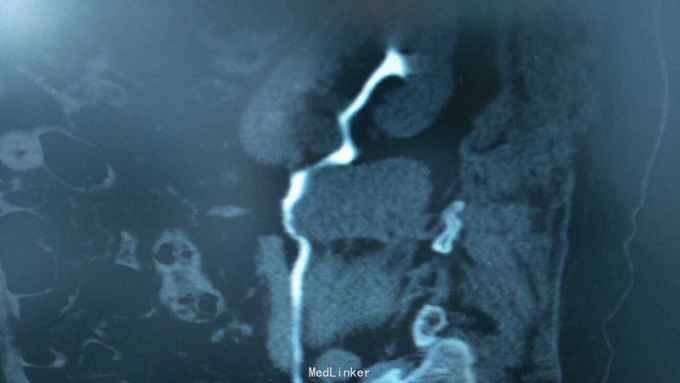

68岁,女性。 主诉:左侧腰痛1年,加重1个月。 病史:1年前无明显诱因出现左侧腰痛,无恶心呕吐,无肉眼血尿。1个月前加重,于外院查泌尿系彩超显示:左肾积液,输尿管显示不清。

诊断:双肾盂旁囊肿 治疗:因患者肾盂未明显受压,疼痛症状不明显,等待观察,暂未予处理。

双侧同时出现的病例并不多见,临床只能通过泌尿系统CTU或增强CT加以鉴别,彩超无法区分肾盂积水及盂旁囊肿。